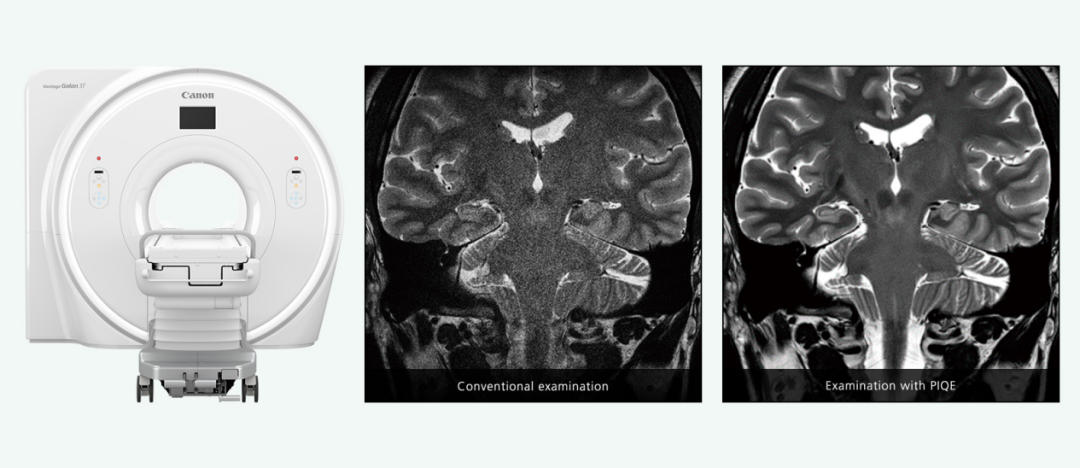

在醫(yī)學(xué)影像中,CT和MRI的分辨率受限于掃描時(shí)間和輻射劑量。超分辨率技術(shù)通過(guò)算法重建低分辨率圖像,提升影像清晰度,尤其在觀(guān)察微小病變和細(xì)節(jié)方面表現(xiàn)出色。例如,基于生成對(duì)抗網(wǎng)絡(luò)(GAN)的CT超分辨率投影生成方法可顯著抑制偽影,提升圖像質(zhì)量。在MRI中,超分辨率技術(shù)可在不增加掃描時(shí)間的情況下,提高圖像分辨率,減少患者等待時(shí)間。

微信圖片_20250214113923.png

Canon PIQE技術(shù)